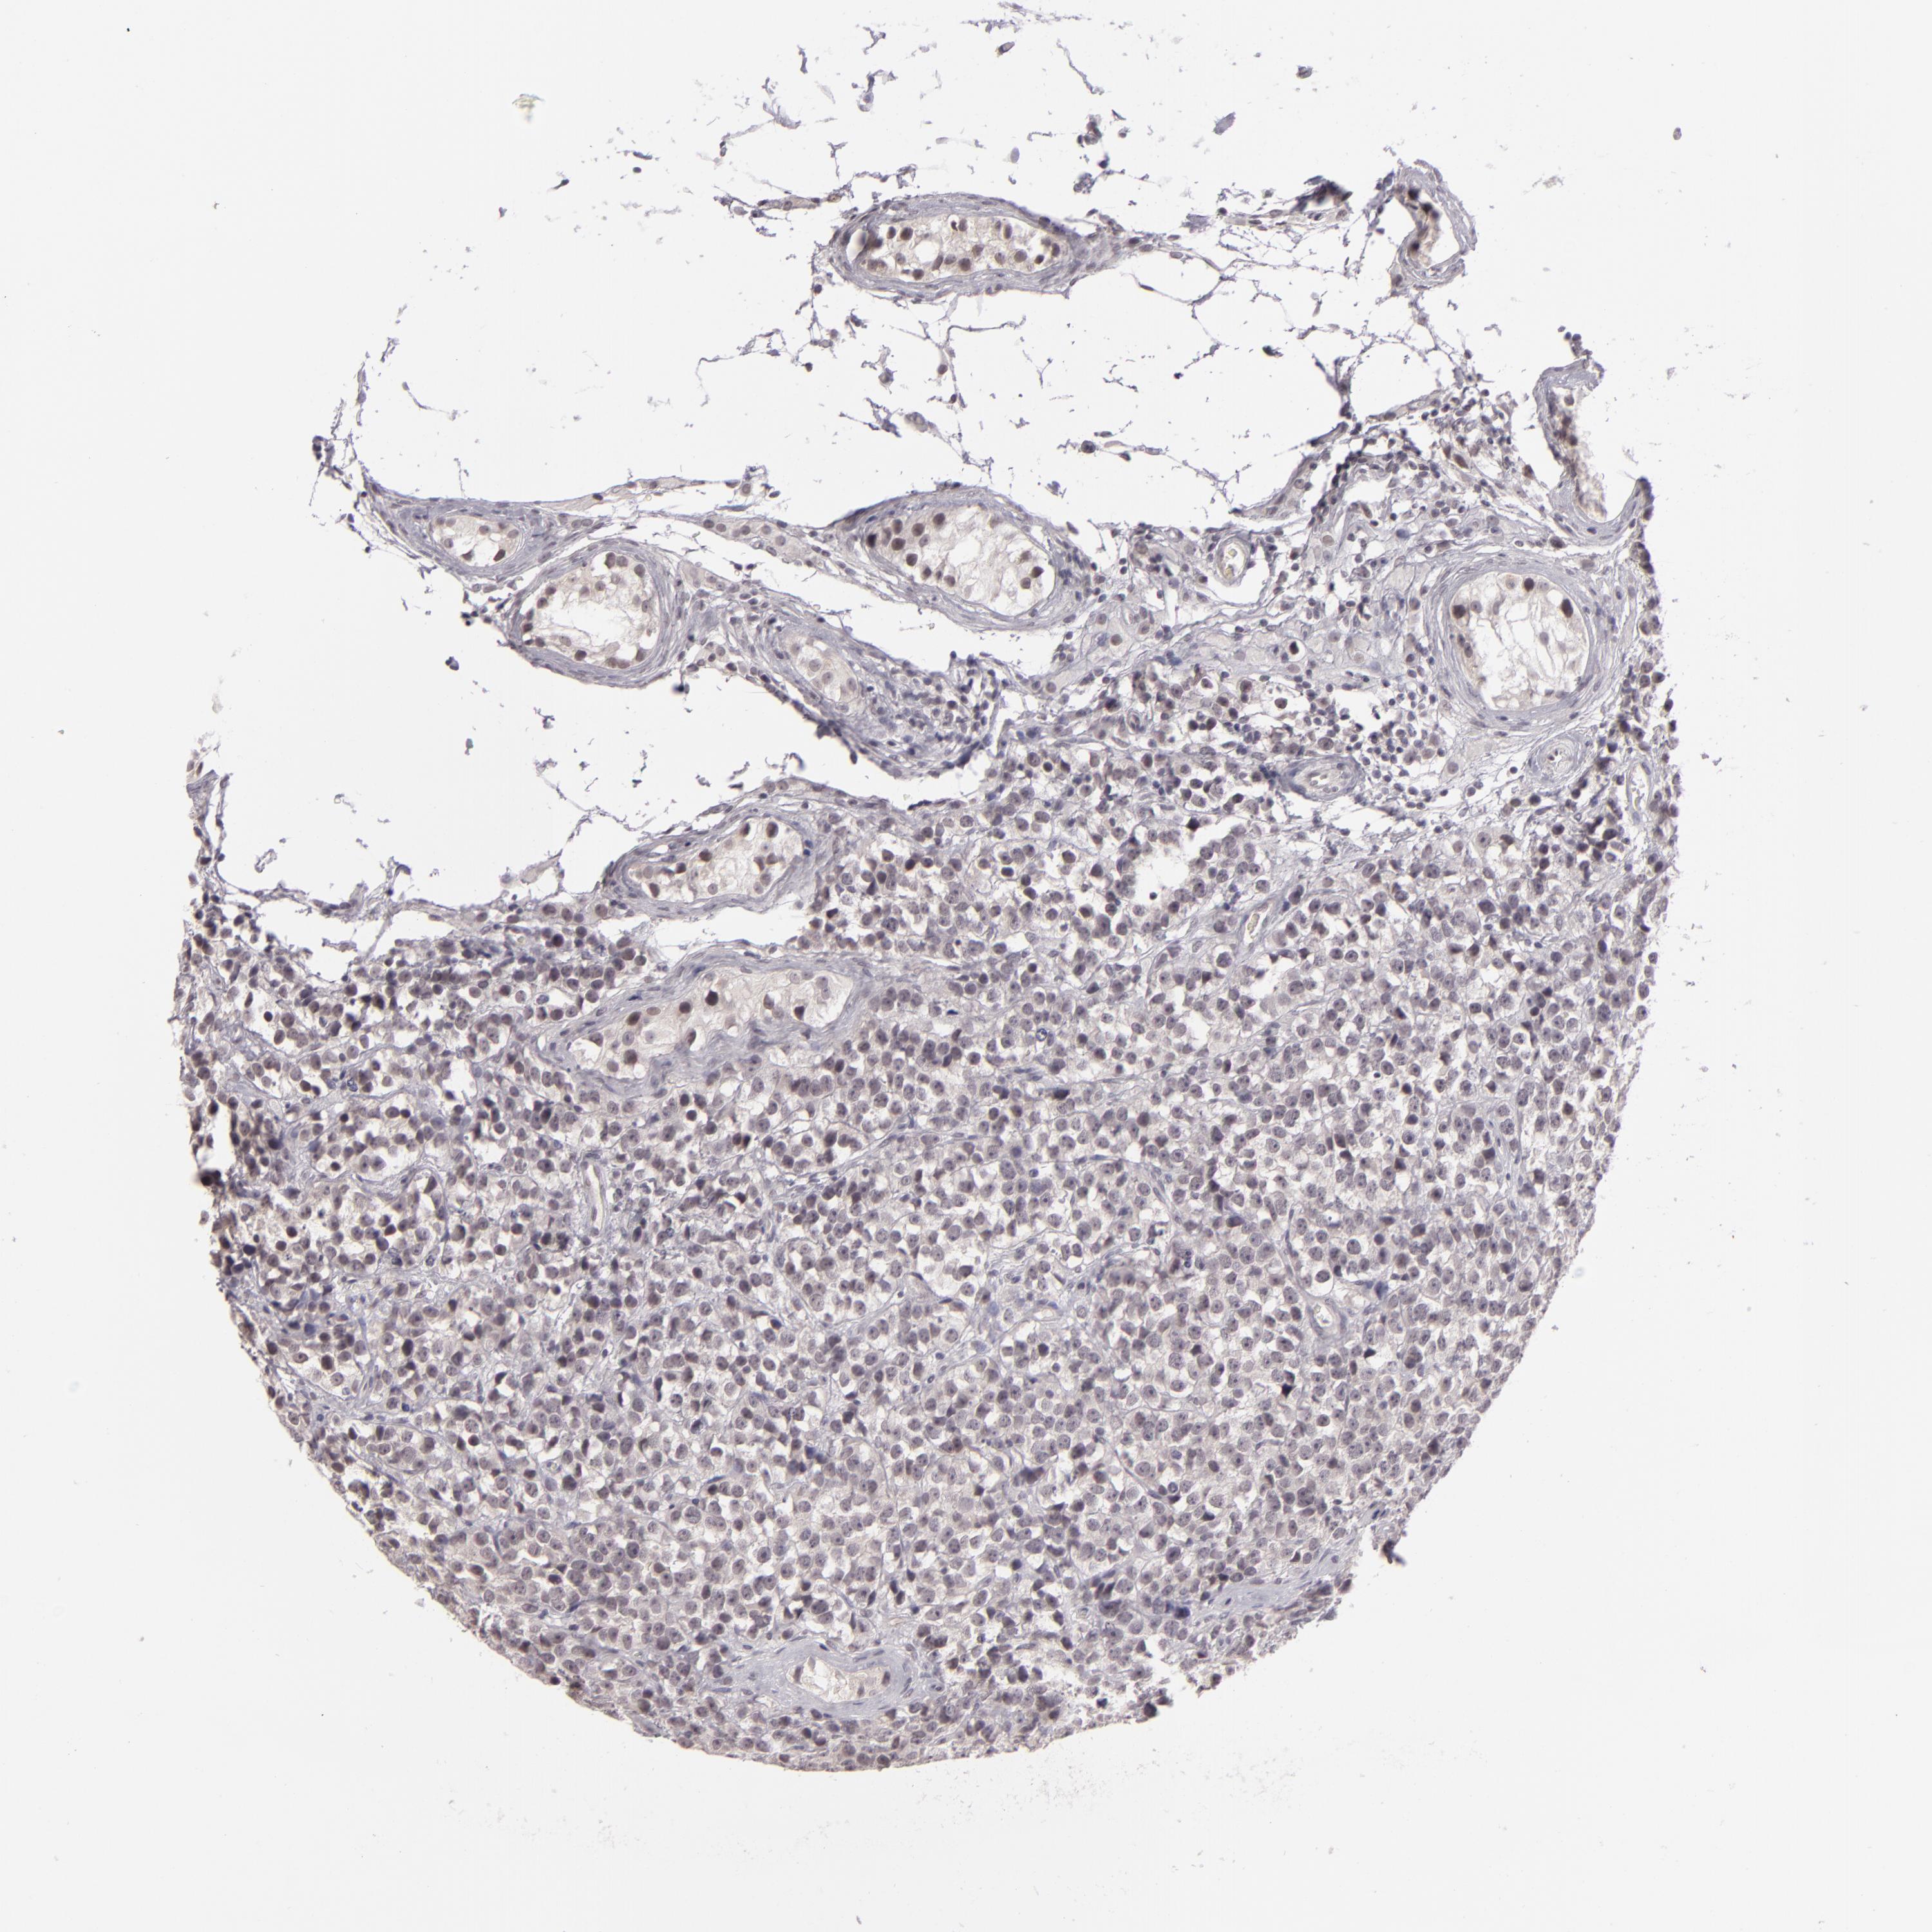

TESTIS CANCER - Protein expressioni

A mouse-over function shows sample information and annotation data. Click on an image to view it in a full screen mode. Samples can be filtered based on level of antibody staining by selecting one or several of the following categories: high, medium, low and not detected. The assay and annotation is described here.

Note that samples used for immunohistochemistry by the Human Protein Atlas do not correspond to samples in the TCGA dataset.

Antibody stainingi

Antibody staining in the annotated cell types in the current human tissue is reported as not detected, low, medium, or high, based on conventional immunohistochemistry profiling in selected tissues. This score is based on the combination of the staining intensity and fraction of stained cells.

Each image is clickable and will lead to virtual microscopy that enables deeper exploration of all samples and also displays staining intensity scores, fraction scores and subcellular localization as well as patient and tissue information for each sample.

Antibody HPA001791

Staining

High

Medium

Low

Not detected

Intensity

Strong

Moderate

Weak

Negative

Quantity

>75%

75%-25%

<25%

None

Location

Nuclear

Cytoplasmic/membranous

Cytoplasmic/membranous,nuclear

Seminoma, NOS

Carcinoma, Embryonal, NOS